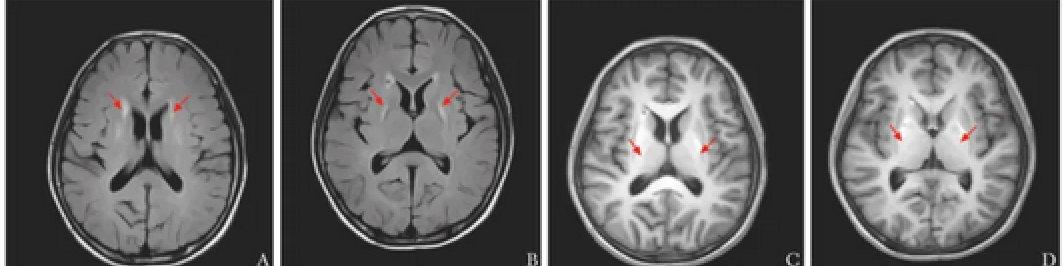

AGS综合征神经系统表现为:颅内多发钙化灶、脑白质病变、脑脊液慢性淋巴细胞增多。

皮肤表现为典型的冻疮样皮疹(A图),少见的有荨麻疹(B图)、雀斑样(C图)、弥漫性银屑病及网状青斑(D图)等。